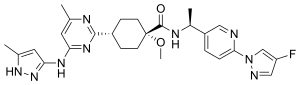

Pralsetinib

IUPAC name

| Chemical and physical data | |

| Formula | C27H32FN9O2 |

| Molar mass | 533.612 g·mol−1 |

SMILES

InChI

Pralsetinib, sold under the brand name Gavreto, is a medication used to treat non-small cell lung cancer (NSCLC) and thyroid cancer.[1] It is used in advanced cases which are RET fusion-positive.[1] It is taken by mouth.[1]